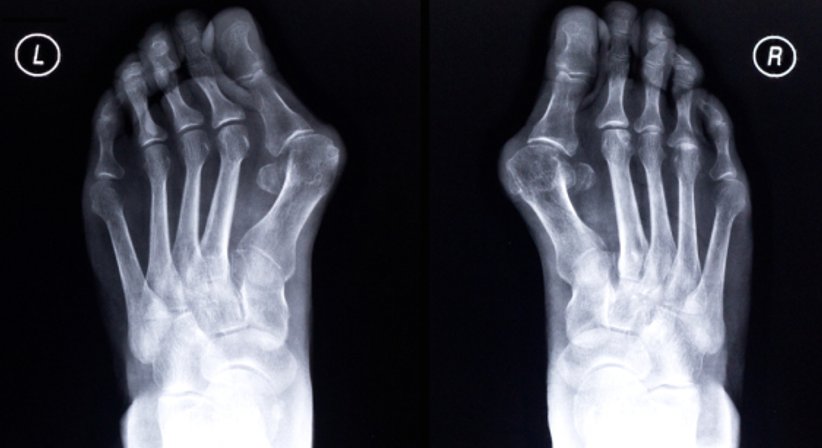

Der Hallux valgus, die häufigste Fehlstellung des vorderen Fußes,

stellt zu Beginn meistens nur ein ästhetisches Problem dar, führt im weiteren Verlauf jedoch häufig zu starken Schmerzen und anderen Beschwerden.

Es handelt sich um eine Fehlstellung der Großzehe, bei welcher diese von ihrer ursprünglichen Position abweicht - das Grundgelenk der Großzehe schiebt sich allmählich nach außen, wobei sich eine für den Hallux valgus charakteristische Wölbung bildet.

Durch die "Verdrehung" der Großzehe werden auch die kleineren Zehen zusammengedrückt; sie weichen aus, was wiederum die Entstehung anderer Fehlstellungen (Krallen- und Hammerzehen) begünstigt.